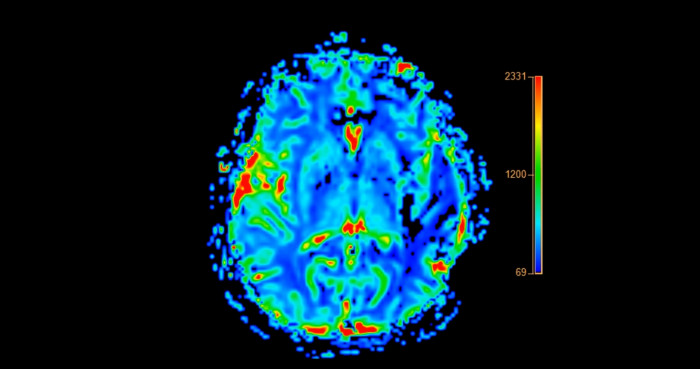

The disease is typically diagnosed through a combination of clinical assessments, cognitive tests, and neuroimaging techniques, which help to rule out other potential causes of cognitive decline. The symptoms of Alzheimer’s disease can vary widely among individuals, but common early signs include forgetfulness, difficulty with problem-solving, confusion about time or place, and changes in mood or personality.